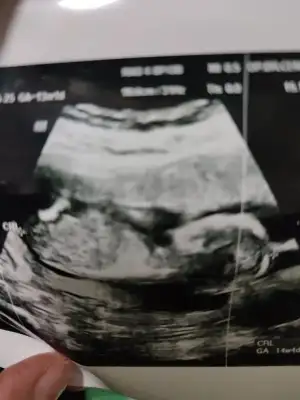

dr soylemeden siz gorun genital nub teorisi ( bebegin cinsiyeti)

9 haftalık görüntü bilen yorum yapabilir mi

• 7E05B8EB-3773-42B4-B1F3-FE327BD38858.webp

7E05B8EB-3773-42B4-B1F3-FE327BD38858.webp

33,5 KB · Görüntüleme: 59